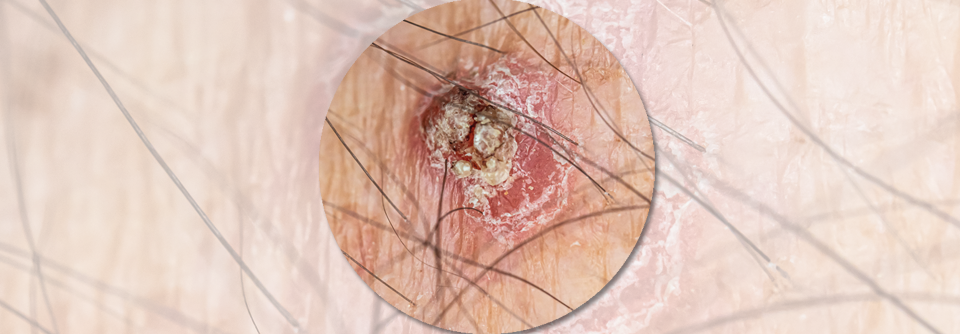

Je nach Substadium ist das Rezidivrisiko bei Melanomen im Stadium III hoch. Je nach Substadium ist das Rezidivrisiko bei Melanomen im Stadium III hoch. © iStock/JodiJacobson

Bei operablen Melanomen des Stadiums III kann je nach Substadium das Rezidivrisiko hoch und die Fünf-Jahres-Überlebenschance gering sein. Darum gibt es bereits zwei kleine Studien zur Kombination des CTLA4-Inhibitors Ipilimumab mit dem PD1-Blocker Nivolumab im neoadjuvanten Einsatz. Tatsächlich ließen sich damit hohe Raten pathologischer Remissionen von bis zu 78 % erzielen.